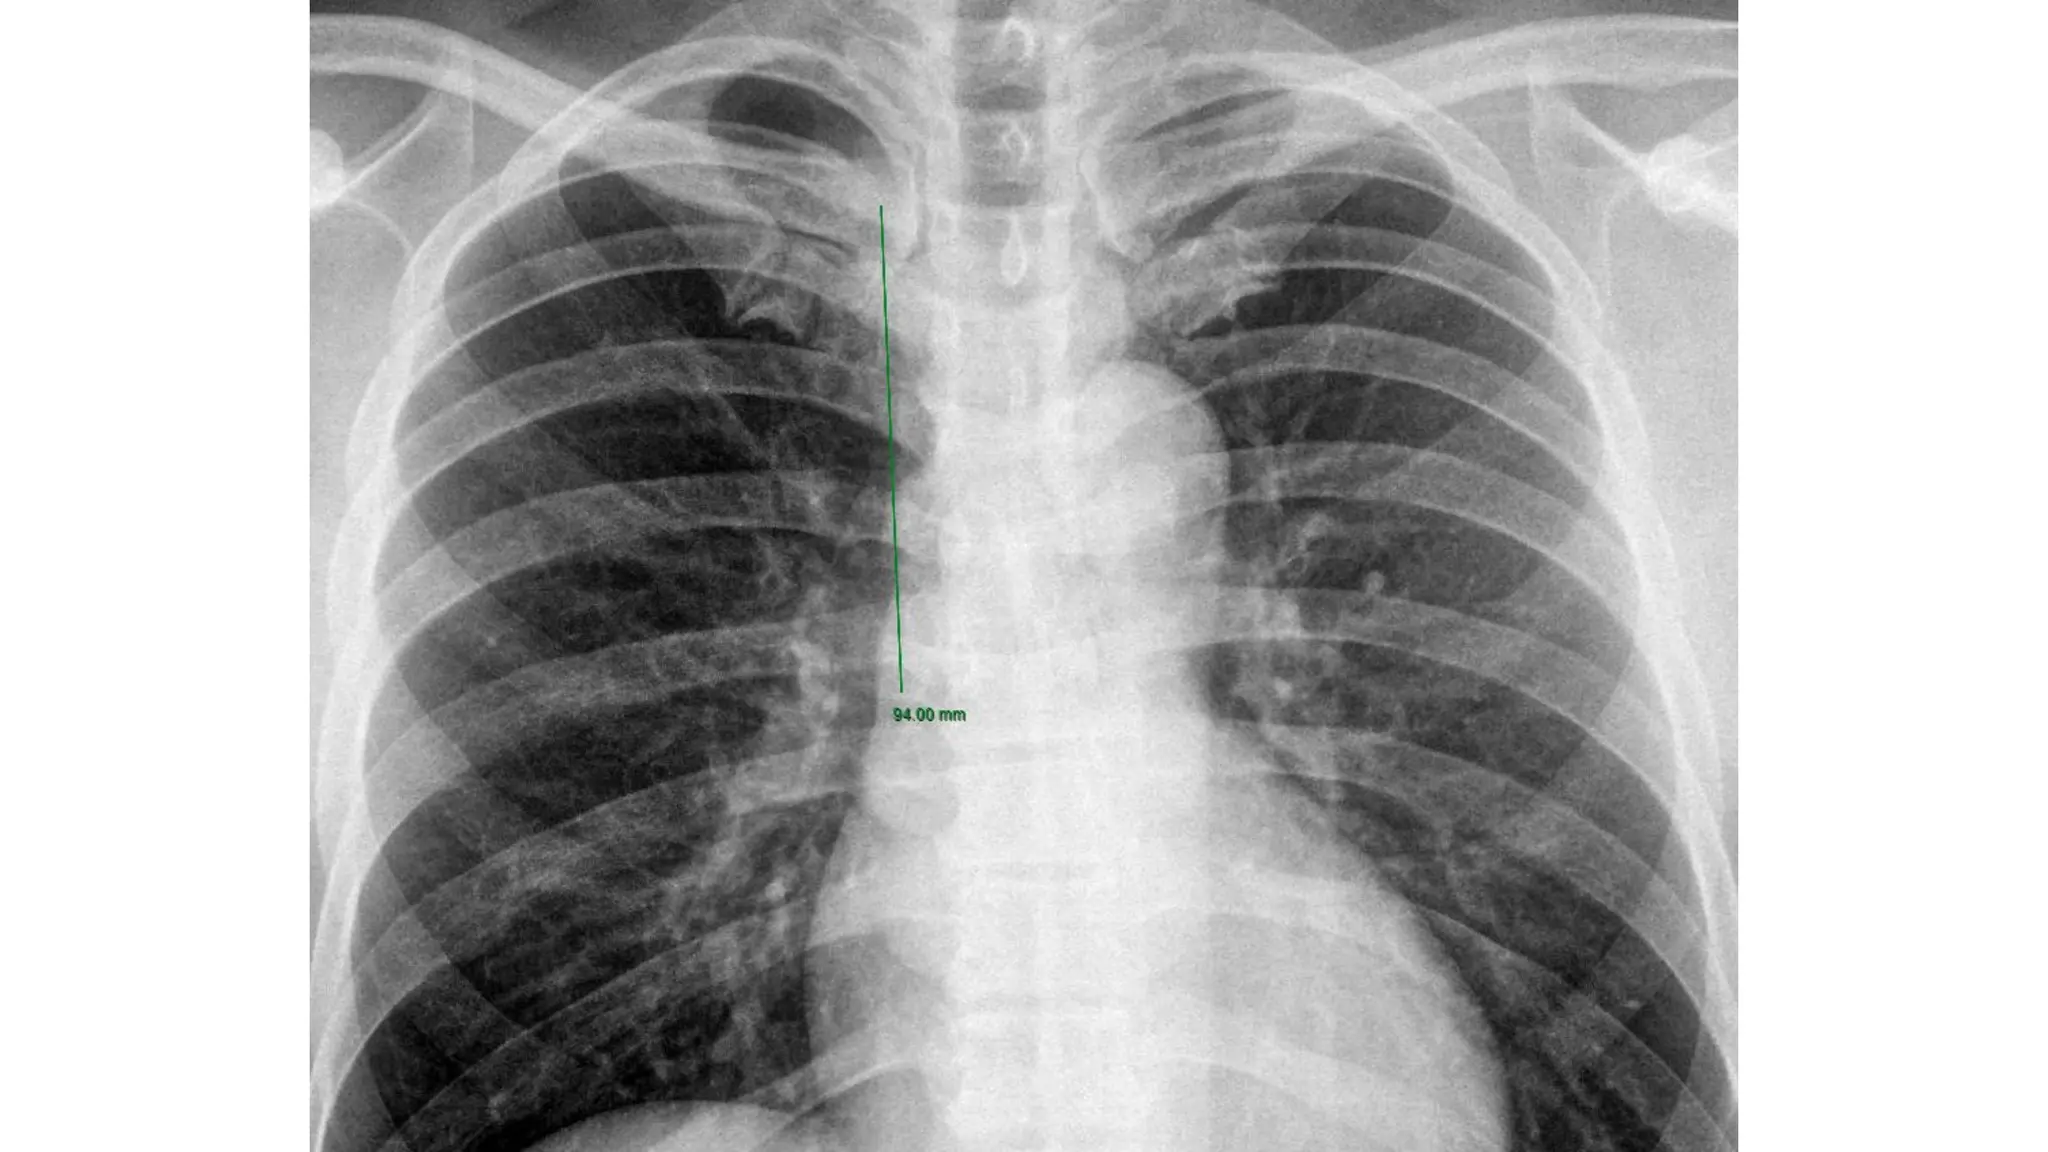

CHỌN MỐC CỐ ĐỊNH CATHETER

Vị trí đầu catheter lý tưởng:

● Cảnh: nhĩ phải

● Đùi: TM chủ dưới

BYT?

Peres 1990:

● cảnh (P) H/10 cm

● cảnh (T) H/10 + 4 cm

● dưới đòn (P) H/10 - 2 cm

● dưới đòn (T) H/10 + 2 cm

ECG? Siêu âm? XQ?